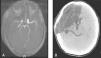

TC craneal sin contraste. A) Área hipodensa con pérdida de la diferenciación entre sustancia blanca y gris que ocupa todo el lóbulo frontal derecho y brazo anterior de la cápsula interna con efecto masa hacia la izquierda. Signo de la arteria cerebral media hiperdensa. B) Área hipodensa que afecta a lóbulos frontal, temporal y parietal derechos, junto a ganglios de la base ipsolaterales, con efecto masa y desplazamiento de la línea media, provocando obliteración del asta temporal derecha y compresión del ventrículo lateral derecho, en relación con herniación subfacial y uncal.

Niño de 12 años, previamente sano, que sufre bruscamente pérdida de la reactividad y tono de segundos de duración. Al recuperar la consciencia presenta hemiparesia izquierda, incluida la cara, dislalia, cefalea holocraneal y un vómito. Es trasladado al hospital comarcal donde se evidencia dicha focalidad y presenta hemiconvulsión derecha que precisa diazepam, fenitoína, perfusión de propofol y ventilación mecánica. La TC craneal es normal. Se traslada a nuestro centro a las 10h del inicio donde, tras la retirada de la sedación y la ventilación mecánica, presenta un Glasgow de 14, hemiparesia y hemihipoestesia izquierdas, con desviación conjugada de la mirada a la derecha. Por sospecha de ictus de la arteria cerebral media (ACM), se repite la TC (15h del inicio), apreciándose hipodensidad fronto-parieto-temporal derecha e hiperdensidad de la ACM derecha. Inicia antiagregación y se descarta patología de troncos supraaórticos, miembros inferiores y cardíaca mediante ecografía-Doppler bidimensional. Tras 12h presenta signos de herniación uncal derecha (fig. 1), se intuba e inicia tratamiento de la hipertensión intracraneal (HIC) con sedoanalgesia profunda, osmoterapia, medidas posturales y normoventilación, pese a lo cual persiste la clínica de HIC con midriasis derecha. Se realiza craniectomía descompresiva derecha con duraplastia y colocación de sensor de presión, manteniendo posteriormente PIC de 15-18cmH2O. Precisó dopamina durante 24h para mantener presión de perfusión cerebral (PPC) > 50mmHg. La angiorresonancia muestra infarto isquémico extenso del territorio de la ACM derecha y en territorio basal de arteria cerebral anterior, con stop proximal en segmento M1 (fig. 2A). Se inicia heparina de bajo peso molecular tras la primera semana y rehabilitación precoz. Tras extubación a los 10 días presenta, junto a focalidad previa, funciones cognitivas conservadas, paresia del III par derecho y disfagia a líquidos.